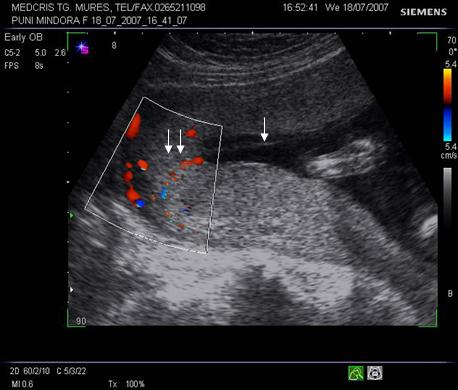

Fig nr 39

Prezinta aceeasi sarcina biamniotica bichoriala,ca in figura precedenta, cu

semnul lambda marcat cu sageata